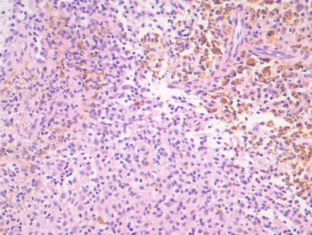

Sikaria, S., Heim-Hall, J., Diaz, E.H. et al. Partial response of a rare malignant metastatic diffuse tenosynovial giant cell tumor with benign histologic features, treated with SCH 717–454, an insulin growth factor receptor inhibitor, in combination with everolimus, an MTOR inhibitor. Targ Oncol 9, 73–79 (2014). https://doi.org/10.1007/s11523-013-0267-8